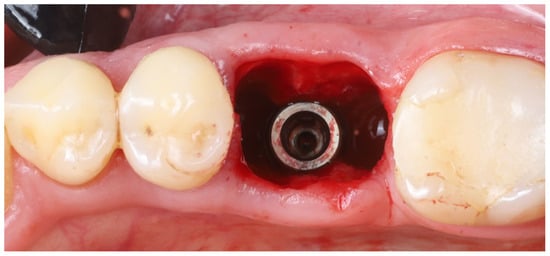

- Implant placement: A dental implant (Megagen Blue Diamond, 4.8 mm diameter × 10 mm length, conical “Deep thread” design) was inserted into the prepared osteotomy. The implant was centered within the socket, with its shoulder positioned roughly 5–6 mm below the level of the surrounding gingival margin (Figure 4). The implant fits snugly between the two buccal shields without exerting undue pressure on them. Primary stability was achieved; the implant had an insertion torque of about 35 N·cm, and verification with a resonance frequency analysis device showed an Implant Stability Quotient (ISQ) exceeding 70. (This high primary stability indicated that the implant was well stabilized in the septal bone despite the immediate placement.)

- Socket sealing with healing cap: The socket orifice was sealed with a large-diameter healing abutment instead of suturing a flap. A wide, 9 mm diameter, and 6 mm height standard healing cap was attached to the implant, which effectively covered the socket opening and conformed to the circumference of the socket (Figure 5). This approach is intended to protect the socket and support the surrounding gingival margins without requiring a flapped closure or graft. No additional bone graft or membrane was placed in the socket; a blood clot was allowed to fill the gaps between the implant and shields [17].